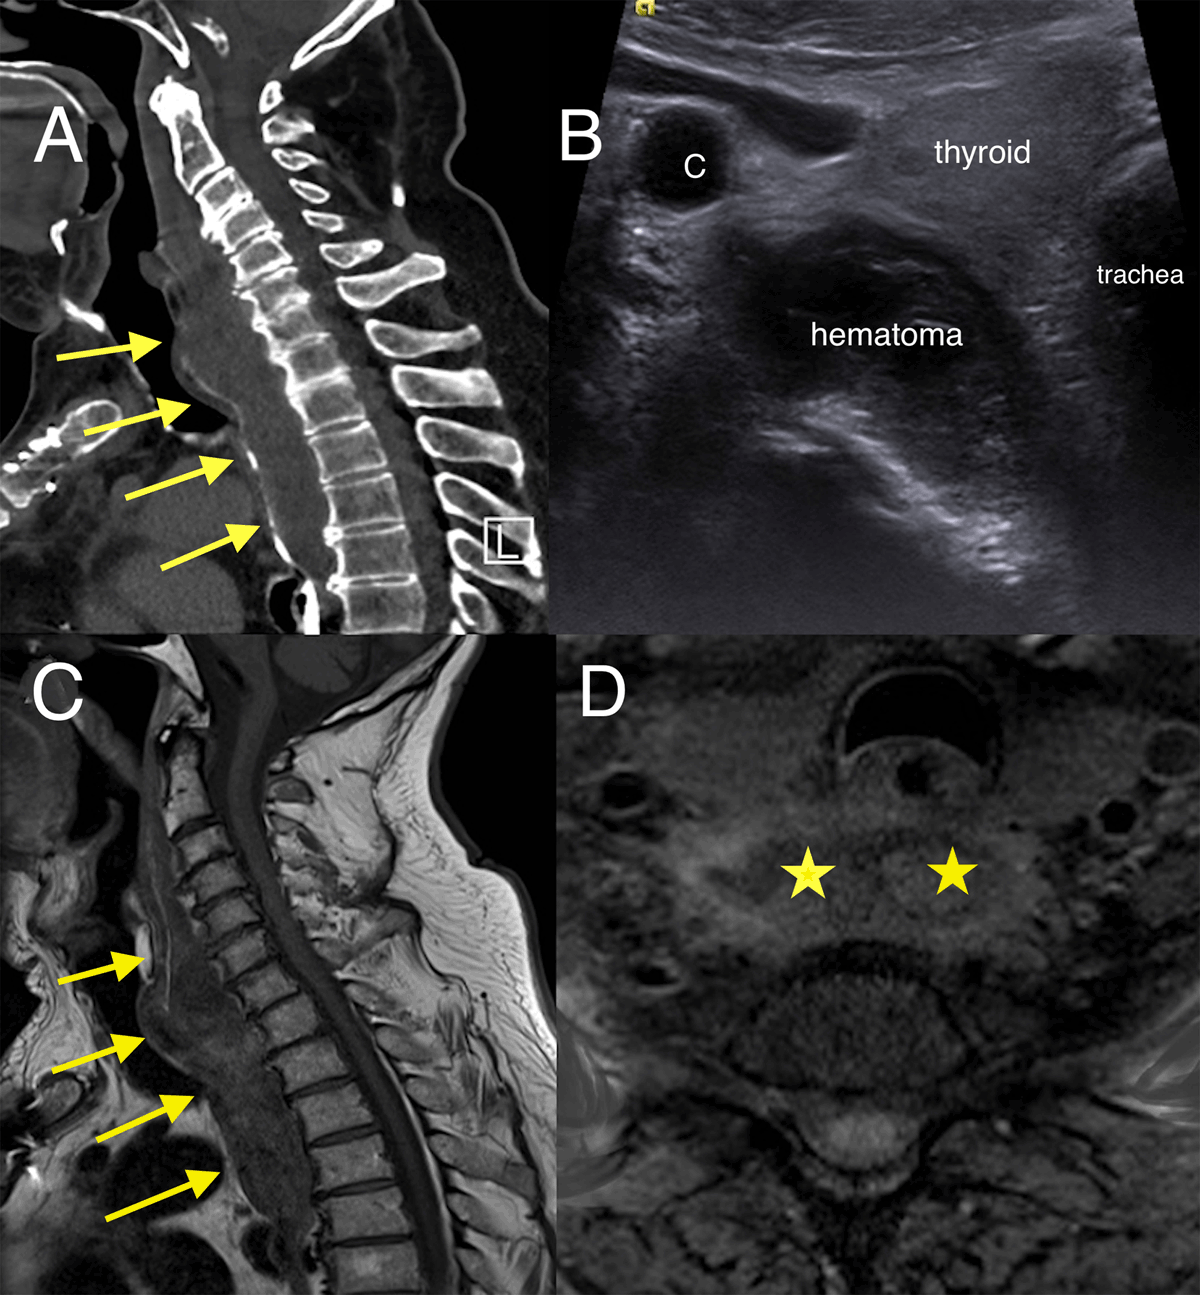

Lateral cervical X-ray showed increased soft tissue thickness of 30 mm in front of C5 (Figure 1, double arrow). Contrast-enhanced computed tomography (CECT) with oral gastrografin administration revealed hematoma extending from the retropharyngeal to the superior mediastinal space without active bleeding or vertebral fracture (Figure 2A, arrows). Axial US image showed a slightly echoic and heterogeneous liquid collection pushing forward trachea and thyroid (Figure 2B).

Figure 2

(A) Sagittal CT image with oral gastrografin administration showing a pre-vertebral hematoma displacing the pharynx (arrows). (B) Axial US image showing the slightly echoic collection pushing forward trachea and thyroid. (C) Sagittal T1-weighted image and (D) Axial T1-weighted image with fat saturation showing the retropharyngeal hematoma on day 7 with methemoglobin hyperintensity (arrows and asterisks).

The hematoma was not drained due to its good tolerance. The patient was monitored closely. On magnetic resonance imaging (MRI) performed seven days later, T1-weighted sagittal (Figure 2C, arrows) and axial sequence with fat saturation (Figure 2D, stars) confirmed methemoglobin hyperintensity. A control MRI carried out three months later showed the disappearance of the hematoma.